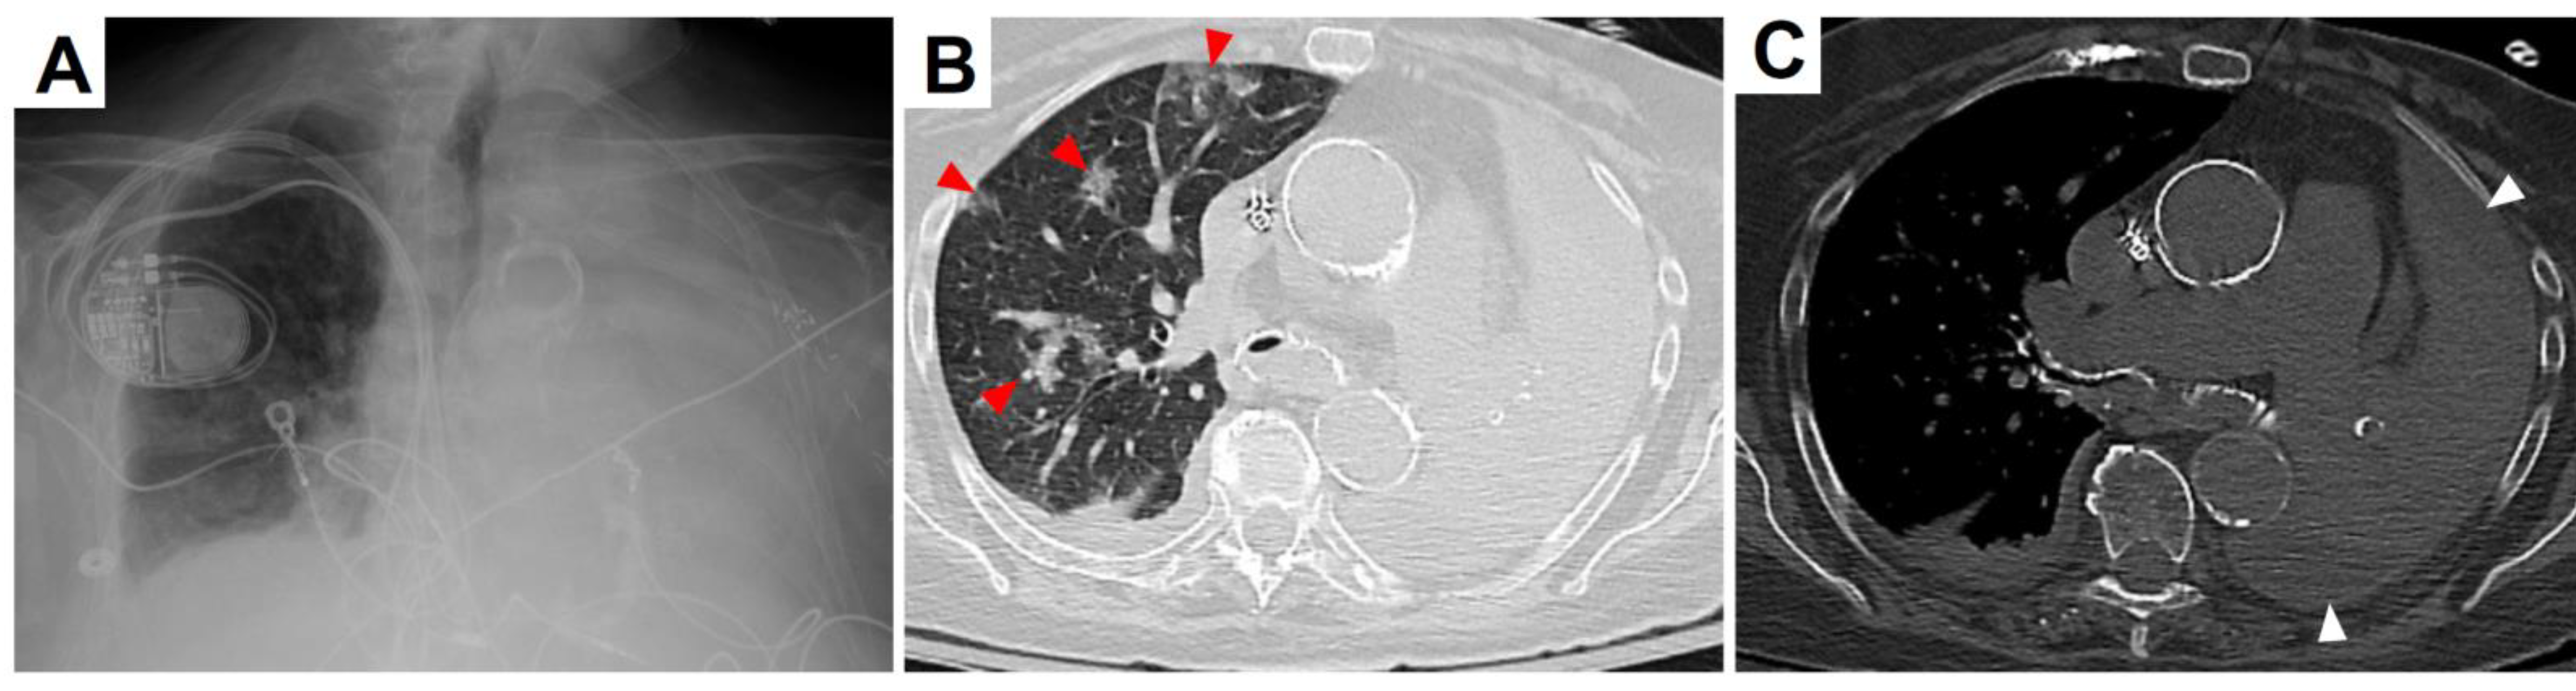

In the emergency department (ED), the patient was afebrile, pale, and in respiratory distress. Her blood pressure was 185/79 mmHg, heart rate 98 beats/minute, respiratory rate 24 breaths/minute, and oxygen saturation 82% on ambient air. Coarse scattered rhonchi were present over the right lung, and breath sounds were markedly decreased on the left. Her Glasgow coma score was 14 (eyes 4, verbal 4, motor 6). Neurological exam revealed neither motor nor sensory deficits. Complete blood count showed a white blood cell count (WBC) of 8.29 thousand/µL (ref. range: 4.31-10.16) with 87% neutrophilia (ref. range: 43-75), hemoglobin 8.8 g/dL (ref. range: 11.5-15.4), and MCV 96% (ref. range: 82-98). The serum creatinine was 3.95 mg/dL (ref. range: 0.6-1.3; patient’s baseline: 3-4) and BUN was 26 mg/dL (ref. range: 5-25). Although numerous leukocytes were present in the urine, urine cultures were negative. Severe inflammation was strongly evidenced by an elevated serum procalcitonin of 295 ng/mL (ref. range: <0.25) and C-reactive protein 128 mg/L (ref. range: <3). Venous blood gas analysis showed a pH of 7.3 (ref. range: 7.3-7.4), pCO2 63.3 mmHg (ref. range: 42-50), and bicarbonate 30.9 mmol/L (ref. range: 24-30). Complete opacification of the left hemithorax and prominent interstitial markings on the right were seen on a chest X-ray performed in the ED (Figure 2A). By chest computed tomography (CT), a massive multiloculated pleural effusion and total lung collapse were evident on the left side. In addition, the right lung had basilar consolidation, scattered ground glass opacities, and subtotal endobronchial obstruction of the mainstem bronchus (Figure 2B,C). While in the ED, two sets of blood cultures were obtained. The patient was given a dose of intravenous (IV) ceftriaxone 1000 mg and IV doxycycline 100 mg. Due to her recent diagnosis of COVID-19, IV tocilizumab 400 mg, IV remdesivir 200 mg, and IV methylprednisolone 35 mg every 12 hours were administered. Upon hospitalization, additional COVID-19 medications included oral (PO) ascorbic acid 1000 mg every 12 hours, PO zinc sulfate 220 mg daily, and PO atorvastatin 40 mg daily.

Figure 2. (A) Chest X-ray showing complete opacification of the left hemithorax. (B) Lung window of chest CT without contrast demonstrating right and left mainstem bronchi with endobronchial debris, scattered right-sided ground glass opacities (red arrowheads) and complete left lung atelectasis. (C) Abdominal window of chest CT without contrast revealing multiloculated pleural effusion surrounding the left lung (white arrowheads).